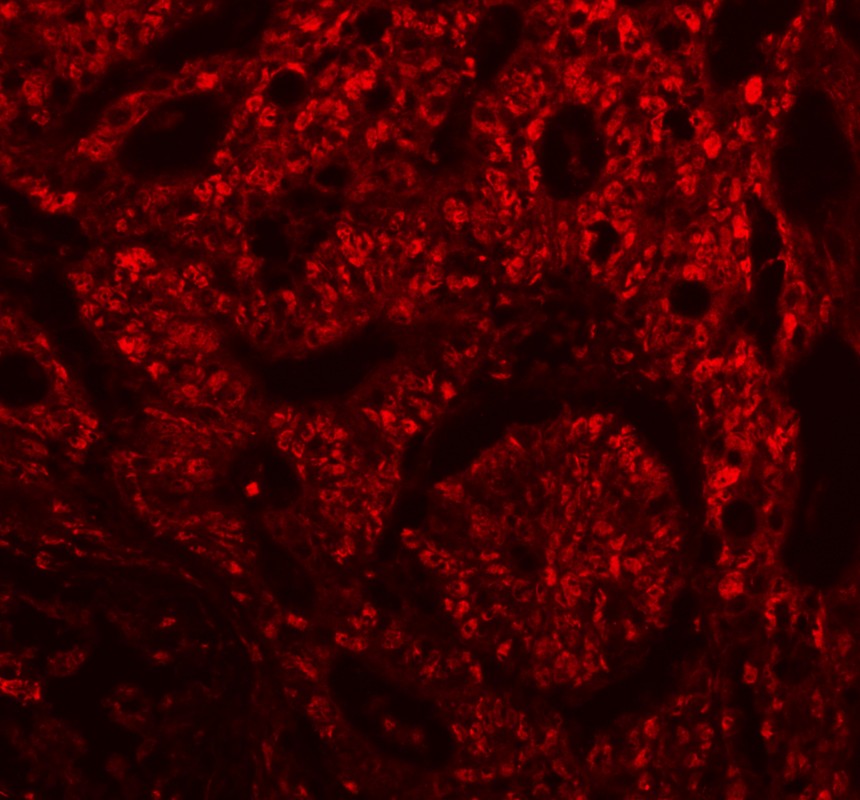

IF analysis of PCNA using anti-PCNA antibody (BM0104).

PCNA was detected in a paraffin-embedded section of human colorectal cancer tissue. The tissue section was incubated with mouse anti-PCNA Antibody (BM0104) at a dilution of 1:100. Fluoro 594 Conjugated AffiniPure Donkey Anti-Mouse IgG (H+L) (red)(Catalog#BA1148) was used as secondary antibody.